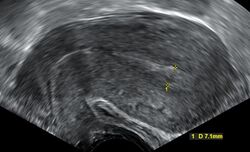

Transvaginal ultrasonography after an episode of heavy bleeding in an intrauterine pregnancy that had been confirmed by previous ultrasonography. There is some widening between the uterine walls, but no sign of any gestational sac, thus, in this case, being diagnostic of a complete miscarriage.

A complete miscarriage is when all products of conception have been expelled; these may include the trophoblast, chorionic villi, gestational sac, yolk sac, and fetal pole (embryo); or later in pregnancy the foetus, umbilical cord, placenta, amniotic fluid, and amniotic membrane. The presence of a pregnancy test that is still positive, as well as an empty uterus upon transvaginal ultrasonography, does, however, fulfil the definition of pregnancy of unknown location. Therefore, there may be a need for follow-up pregnancy tests to ensure that there is no remaining pregnancy, including ectopic pregnancy.[citation needed]